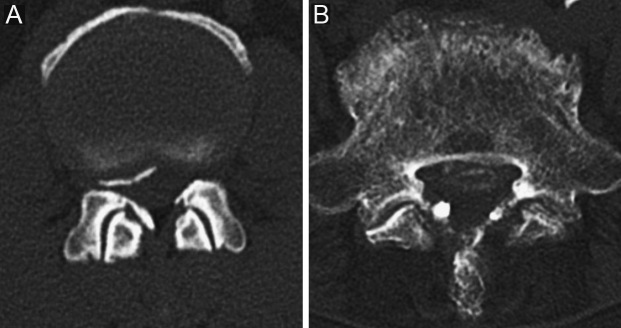

This study aimed to determine the prevalence of lumbar ligamentum flavum lesions and identify correlations between radiological and pathological findings. We conducted an observational cross-sectional study of 349 patients (lumbar: n = 296, thoracic: n = 39, lumbar and thoracic: n = 14, mean age: 69 ± 12 years, male: 74%) who underwent posterior surgery for thoracolumbar spinal canal stenosis between January 2008 and April 2023 at our hospital.Computed tomography (CT) revealed that the prevalence of ligamentum flavum lesions defined as a high-density area with a CT value of 200 Hounsfield Unit or higher in the lumbar and thoracic spine was 47% (147/310) and 85% (45/53), respectively. CT showed that most patients had radiologically suspected ossification in the lumbar (90%) and thoracic spine (98%) than radiologically suspected calcification. Lumbar lesions were thinner than the thoracic lesions (2.5 vs 3.7 mm, p < 0.01). Pathological examinations were performed in specimens collected from 34 cases (lumbar: n = 13, thoracic: n = 21), and ossification was found in 62% (8/13) and 95% (20/21) of lumbar and thoracic lesions (p = 0.02), respectively. Lastly, ossification was confirmed pathologically in 72% (8/11) and 95% (19/20) of lumbar and thoracic lesions that showed ossification on imaging (p = 0.13), respectively. The literature review revealed that the prevalence of the lumbar ligamentum flavum lesions varied from 1.5 to 35% and the patient population was mostly asymptomatic.Collectively, we found that the prevalence of lumbar ligamentum flavum lesions in symptomatic patients was greater than previously reported. Histologically confirmed ossification was less common in lumbar lesions than in thoracic lesions.